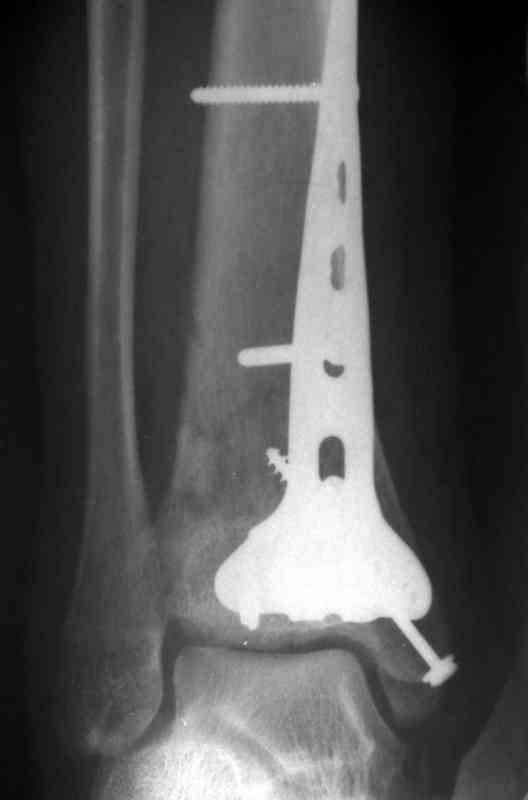

Re: Perelom N/3 kostei goleny

Дрягин В. 04 Январь 2007, 13:28

Кстати, при переломах переднего края по классификации АО В-3 при переломах пилона пластина укладывается по передней поверхности. Она достаточно тонкая и эластичная, не надо этого бояться. Посылаю три снимка.